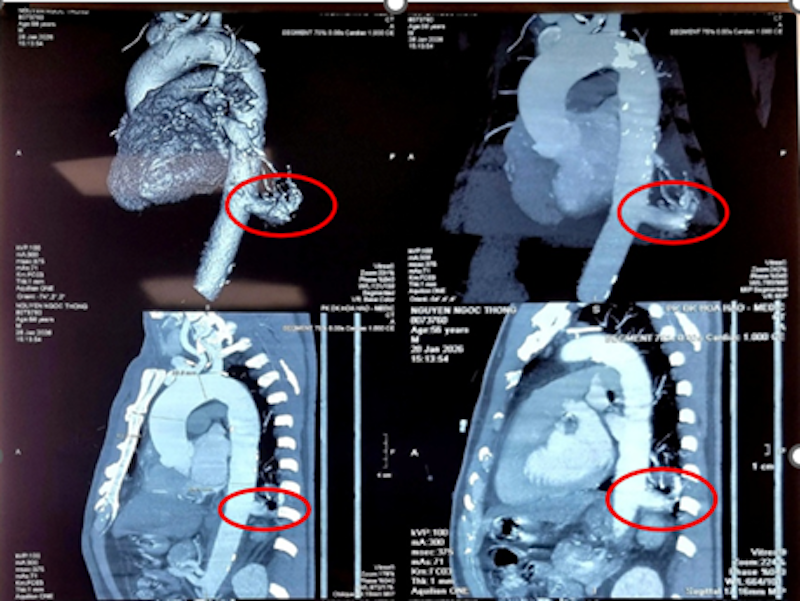

Tổn thương của bệnh nhân có kích thước 23 x 26mm, đặc biệt được nuôi bởi một nhánh động mạch xuất phát trực tiếp từ động mạch chủ xuống, đường kính tới 17mm.

Hình chụp tình trạng ngực của bệnh nhân.

Theo Ths BSCKII Nguyễn Văn Việt Thành - Trưởng Khoa Ngoại Lồng ngực – Bướu cổ Bệnh viện Bình Dân, khó khăn lớn nhất là xử lý mạch máu lớn, dễ vỡ và dính do viêm mạn tính. Chỉ một sai sót nhỏ có thể dẫn đến biến chứng chảy máu nghiêm trọng.